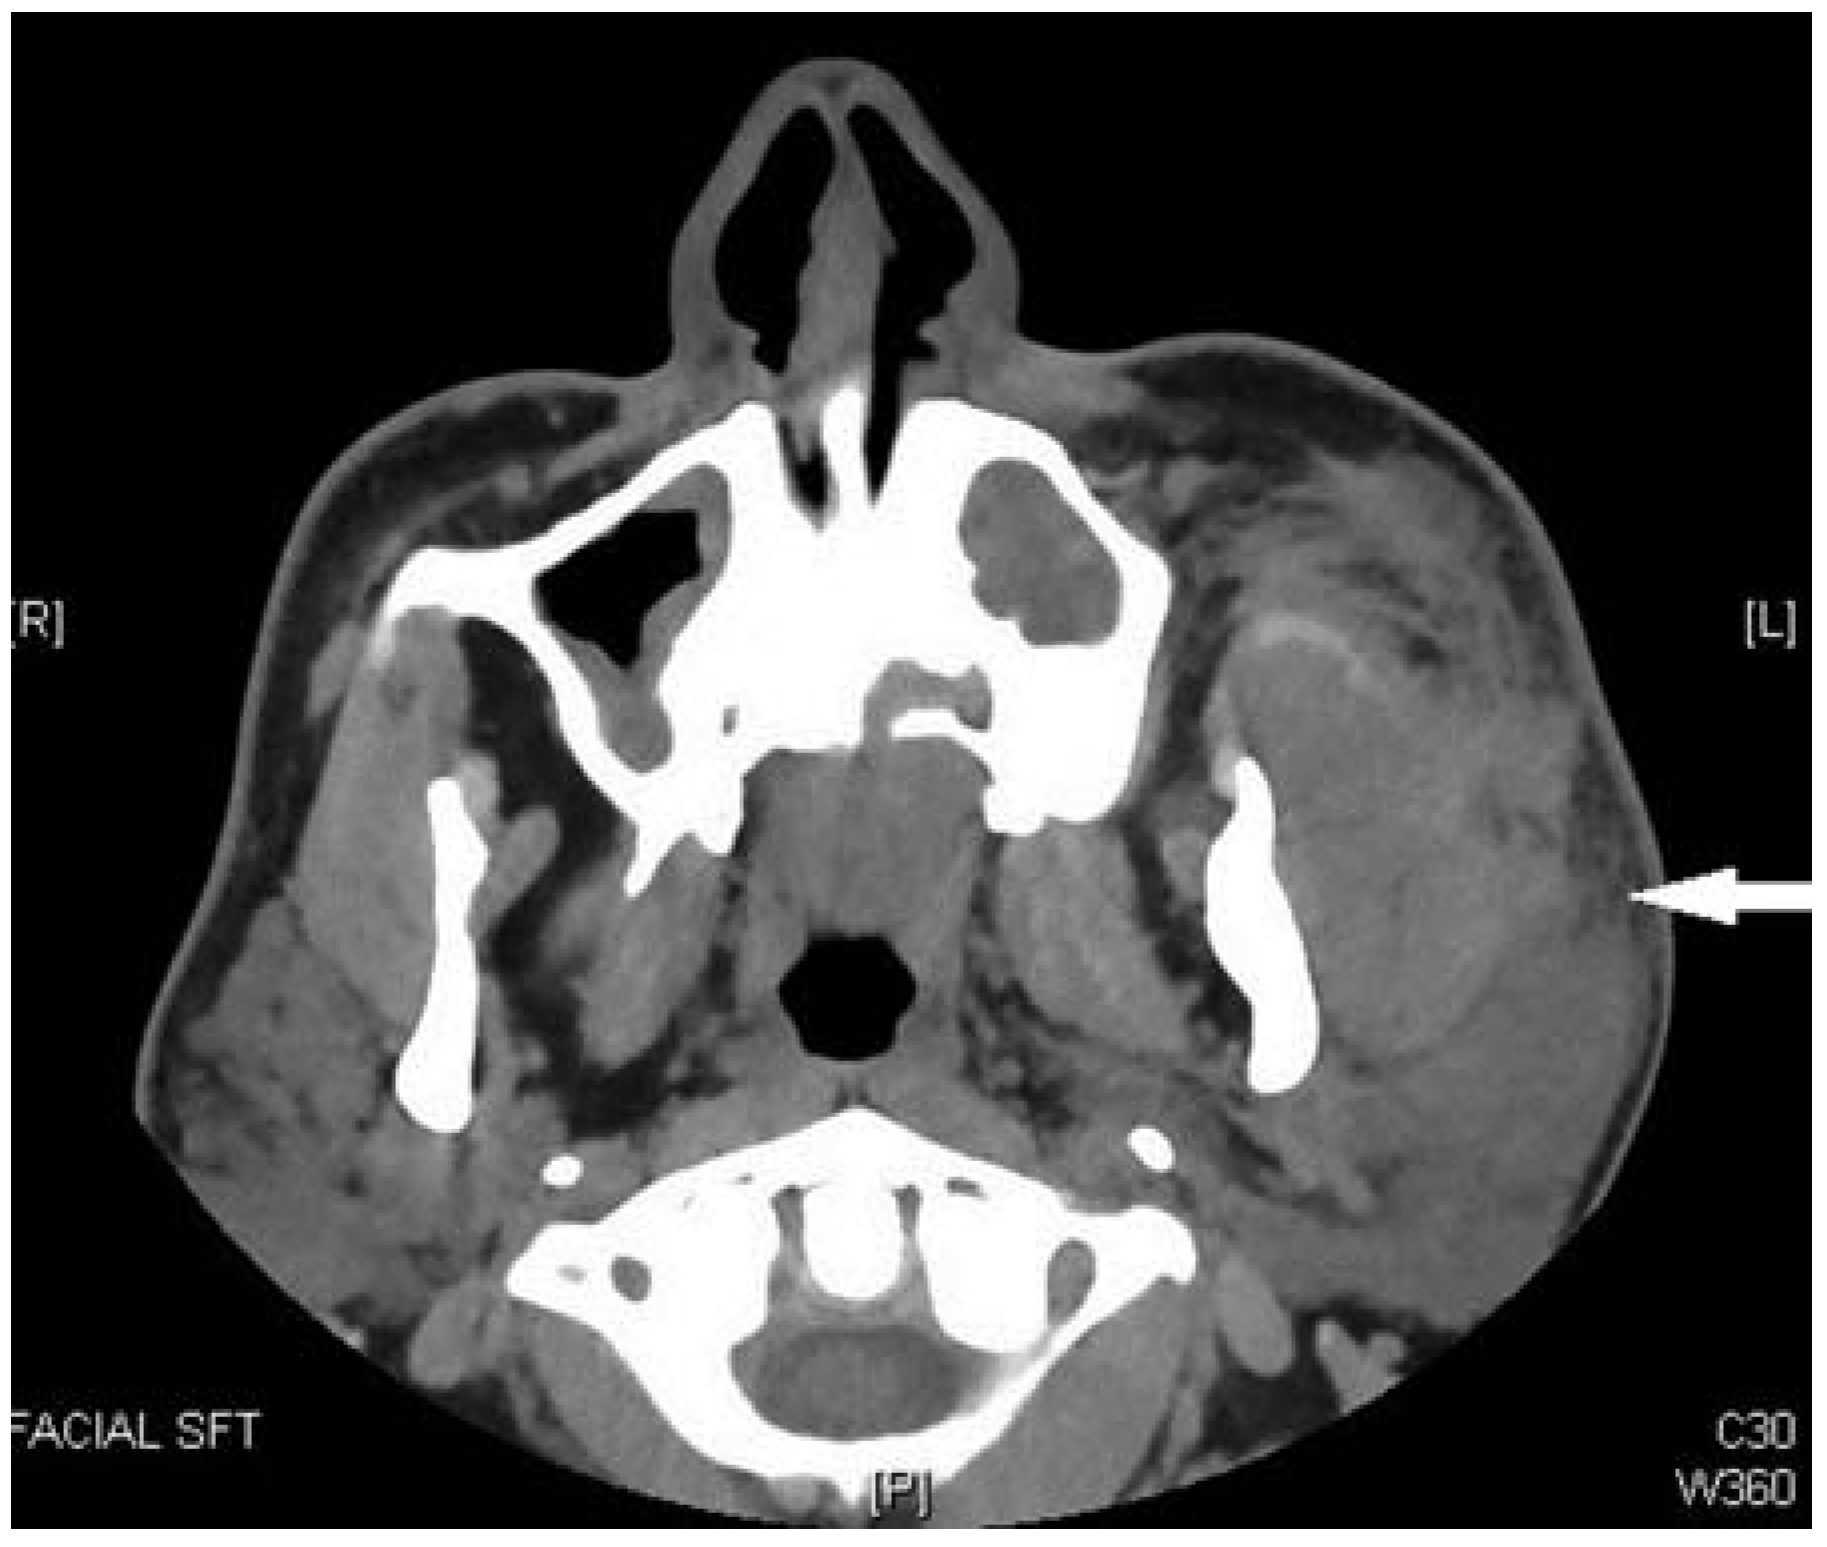

Computed tomography (CT) of the face was positive for a minimally displaced fracture of the left mandibular angle that was continuous with the periodontal ligament space of an erupted nonfunctional lower left third molar (Figure 1a–d). Inaddition to left mandibular angle fracture, the radiologist noted left-sided soft-tissue fullness that was thought to represent a possible hematoma that was 3.4 × 5.5 cm (Figure 2).

In the case presented, disruption of the glandular substance was evident on the initial CT, but was initially interpreted as representing a possible hematoma. This case illustrates the need for careful assessment of soft tissues on initial CT scans taken for maxillofacial trauma. A high index of suspicion for soft tissue injury should be maintained while reviewing scans to ensure diagnoses are not missed.

Figure 2. Preoperative CT scan showing left-sided perimandibular fluid collection. This was initially read as a possible hematoma by the radiologist. Further inspection shows an intracapsular parotid fluid collection consistent with a sialocele.